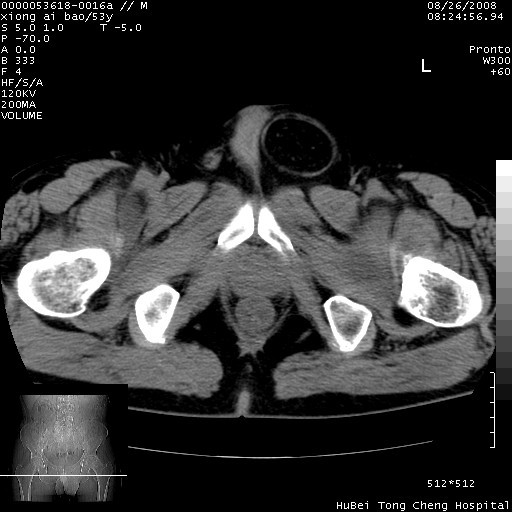

标题: CT15583:M,53Y。请老师指教分析骨盆及其他病变。 [打印本页]

标题: CT15583:M,53Y。请老师指教分析骨盆及其他病变。

双侧股骨头无菌坏死,左侧腹股沟斜疝。

非常典型病例,双侧股骨头坏死伴双髋关节周围软组织肿胀,左腹股沟疝。

双侧股骨头坏死伴双髋关节周围软组织肿胀,左腹股沟疝。

双侧髋关节肿胀明显,感觉还不能排除结核。

考虑双侧髋关节结核,左侧腹股沟疝